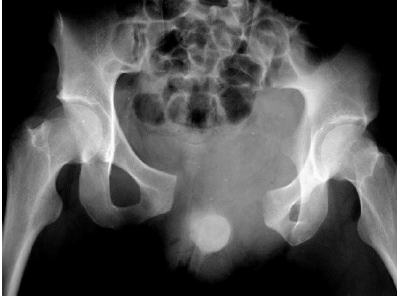

A imagem, abaixo, demonstra comprometimento:

Provas